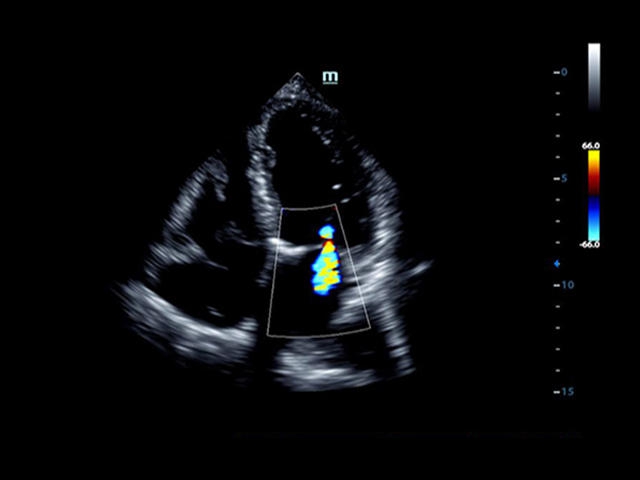

Mindray DC-8 Exp – это ультразвуковой аппарат с архитектурой mQuadro и функцией эластографии Natural Touch. Он оснащен высококлассным 21-дюймовым TFT-монитором с разрешением Full HD. Данный аппарат представляет интерес для специалистов, занимающихся обследованием мягких тканей с использованием эластографии. Режим объемного 4D-сканирования позволяет получать максимально точные диагнозы, сокращая количество неэффективных процедур.

Mindray DC-8 Exp оснащен новым поколением датчиков с увеличенным количеством элементов и инновационной технологией "3T". Это позволяет достичь высокой детализации и качества изображения. Благодаря новейшей технологии iFlow, можно визуализировать даже самые мелкие сосуды и кровеносные пути.

• LVO - опция проведения исследования левого желудочка сердца с применением контрастных веществ;

• LVO - опция проведения исследования левого желудочка с применением контрастных веществ